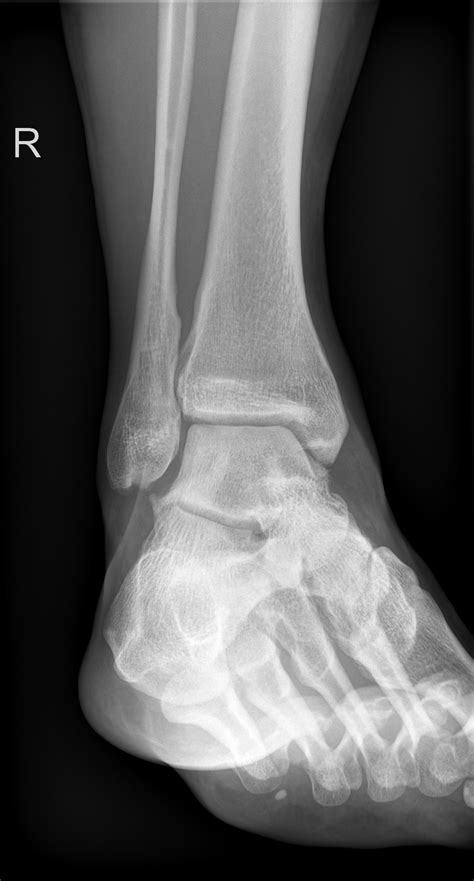

Injuries to the ankle can be debilitating, and one of the more serious conditions is a Lateral Malleolus Fracture. This type of fracture involves the outer part of the ankle, specifically the lateral malleolus, which is the bony prominence on the outer side of the ankle. Understanding the causes, symptoms, diagnosis, and treatment options for a Lateral Malleolus Fracture is crucial for anyone who has experienced an ankle injury or is at risk of one.

The lateral malleolus is a bony protrusion at the distal end of the fibula, one of the two bones in the lower leg. It forms the outer part of the ankle joint and provides stability and support. The lateral malleolus works in conjunction with the medial malleolus (the inner part of the ankle) to create a stable platform for the ankle joint. When a fracture occurs in the lateral malleolus, it can significantly impact the ankle’s stability and function.

Diagnosing a Lateral Malleolus Fracture

Diagnosing a Lateral Malleolus Fracture involves a combination of physical examination and imaging tests. The diagnostic process typically includes:

• Physical Examination: A healthcare provider will assess the ankle for swelling, tenderness, and deformity. They may also check the range of motion and stability of the joint.

• Imaging Tests:

• X-rays: Standard X-rays can reveal the presence and extent of the fracture. Multiple views may be taken to get a comprehensive picture.